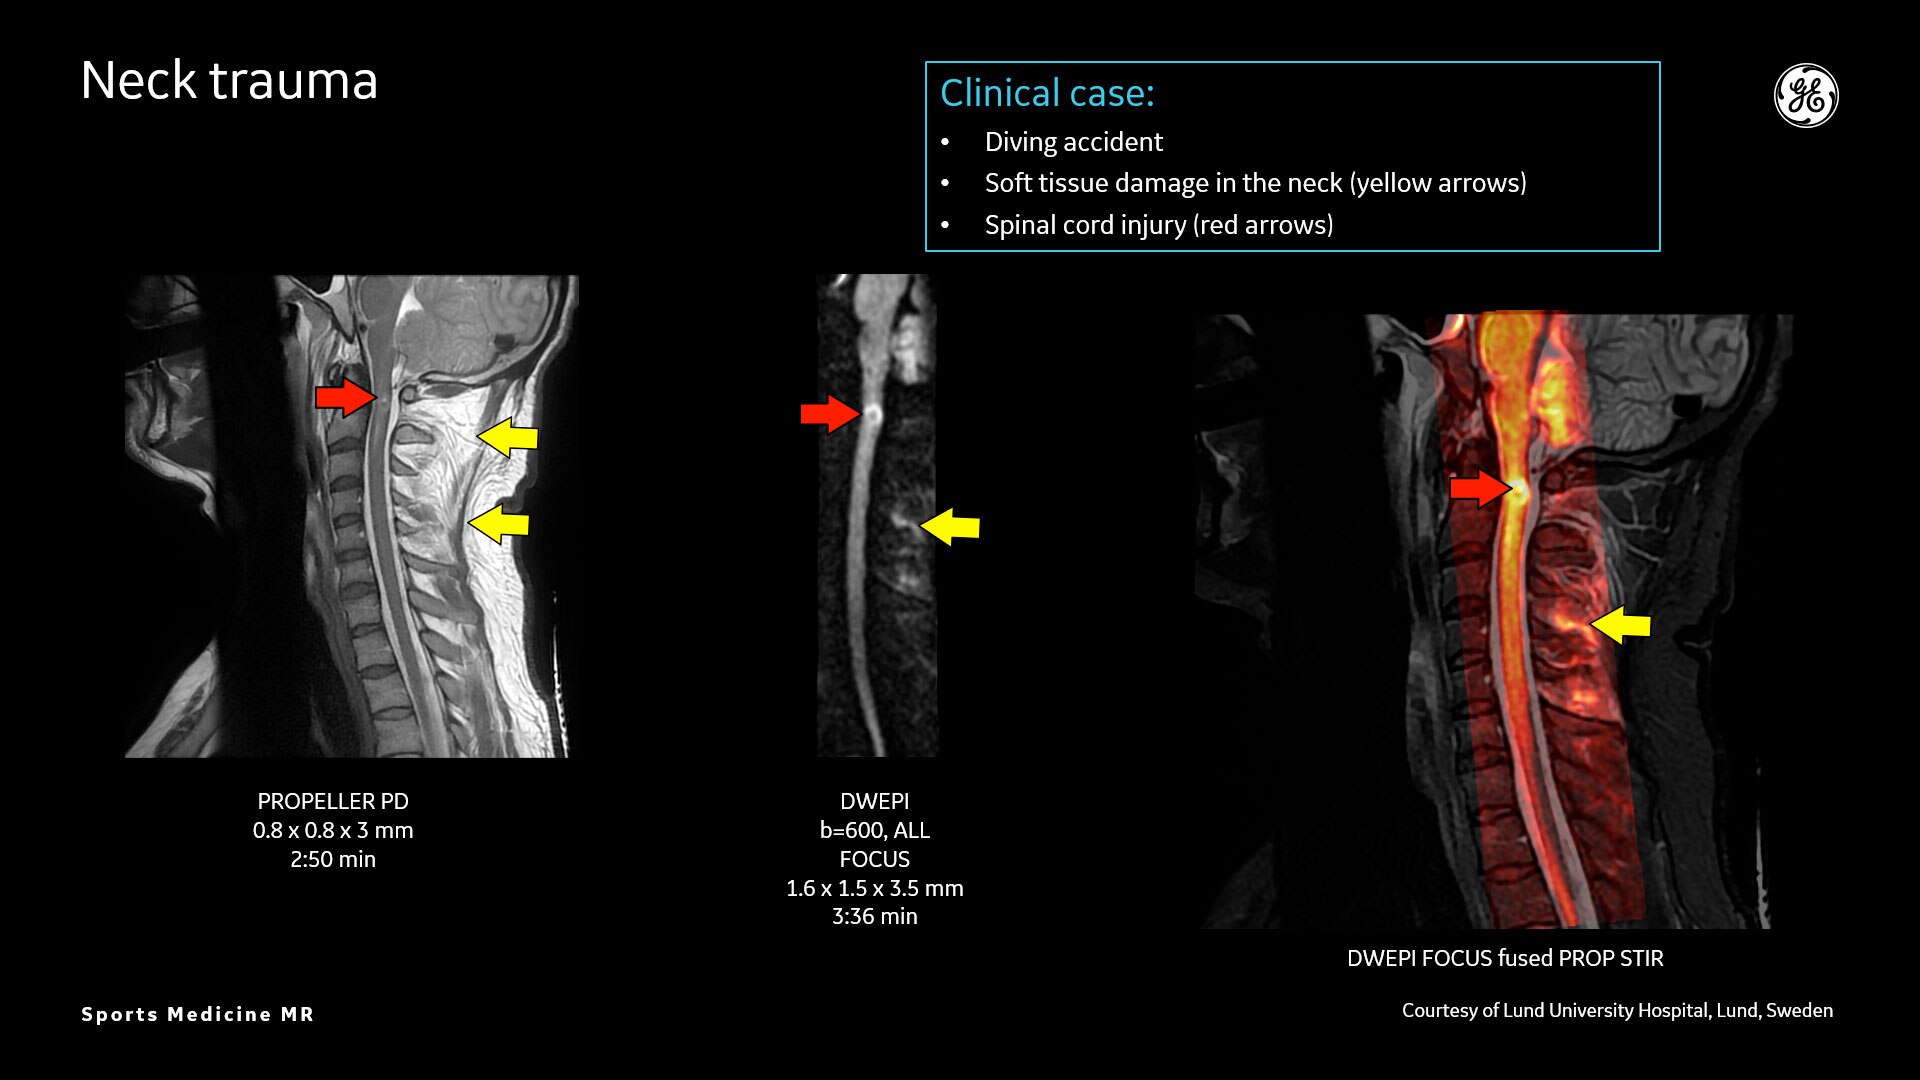

MR lacks ionizing radiation, and is well-suited for longitudinal evaluation of injury in adolescent athletes. The recent introduction of the three dimensional zero-TE (oZTEo) application provides exceptional bone contrast and, like CT, can be reformatted into any arbitrary plane.

AIR™ Recon DL provides high-resolution images with increased SNR at markedly reduced scan times. This technology optimizes the depiction of even small injuries, such as meniscal, labral and ligament tears. The reduction in scan times increases flexibility for individually tailored MR protocols with an additional oZTEo sequence for detailed fracture assessment.